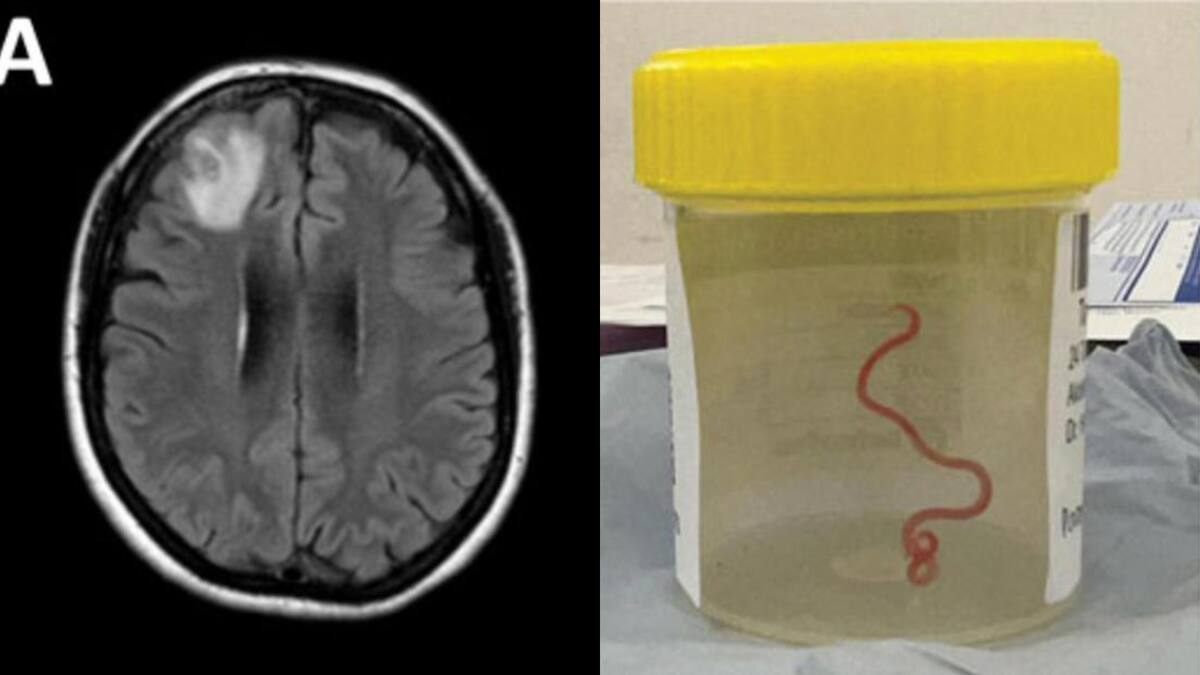

Un grupo de neurocirujanos extrajeron del cerebro de una mujer australiana una lombriz intestinal viva de ocho centímetros, el primer caso de este tipo en humanos, según informaron este martes fuentes académicas.

El parásito, identificado como Ophidascaris robertsi, es común en las serpientes pitones diamantina, una especie endémica de Australia.